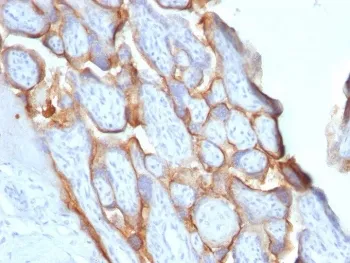

- Description: This antibody reacts with a protein of 22kDa, identified as beta subunit of HCG. It does not cross react with the alpha subunit. HCG is a glycoprotein which is secreted in large quantities by normal trophoblasts. It is present only in trace amounts in non-pregnant urine and sera but rises sharply during pregnancy. HCG is composed of two non-identical, non-covalently linked polypeptide chains designated as the alpha and beta subunits. The alpha subunit is identical to that of thyroid stimulating hormone (TSH), follicle stimulating hormone (FSH), and luteinizing hormone (LH). HCG-beta antibody detects cells and tumors of trophoblastic origin such as choriocarcinoma. Large cell carcinoma and adenocarcinoma of the lung demonstrate antibody positivity in 90% and 60% of cases respectively; 20% of lung squamous cell carcinomas are positive. HCG expression by non-trophoblastic tumors may indicate aggressive behavior.

- Applications: IHC-P